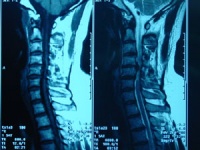

2CT的MRI检查:重症患者或不典型的病例在诊断有困难时,可考虑作脊髓碘油造影CT扫描和磁共振等特殊检查以明确诊断及突出部位

典型腰椎间盘突出CT[编辑 | 编辑源代码]

L4-5间盘层面可见后突丘状软组织影,前后径5mm ,居中偏右,CT值78hu,椎管前后径8mm,硬膜囊明显受压,L5-6间盘层面可见后突丘状软组织影,前后径4mm ,居中偏右,CT值71hu,余所扫各椎间盘层面均未见明显膨突征象。

3D: 生理曲度存在,椎体;附件未见异常,间隙无狭窄。

印象: L4-5;5-S1 椎间盘突出症,以L4-5为著伴继发椎管狭窄。